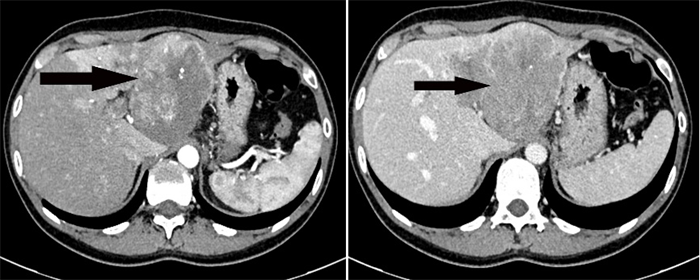

患者1,33歲女性,因“腹部脹痛不適半月”入院,經(jīng)CT檢查提示肝左葉巨大占位性病變,伴門靜脈左支癌栓形成,考慮肝惡性腫瘤。